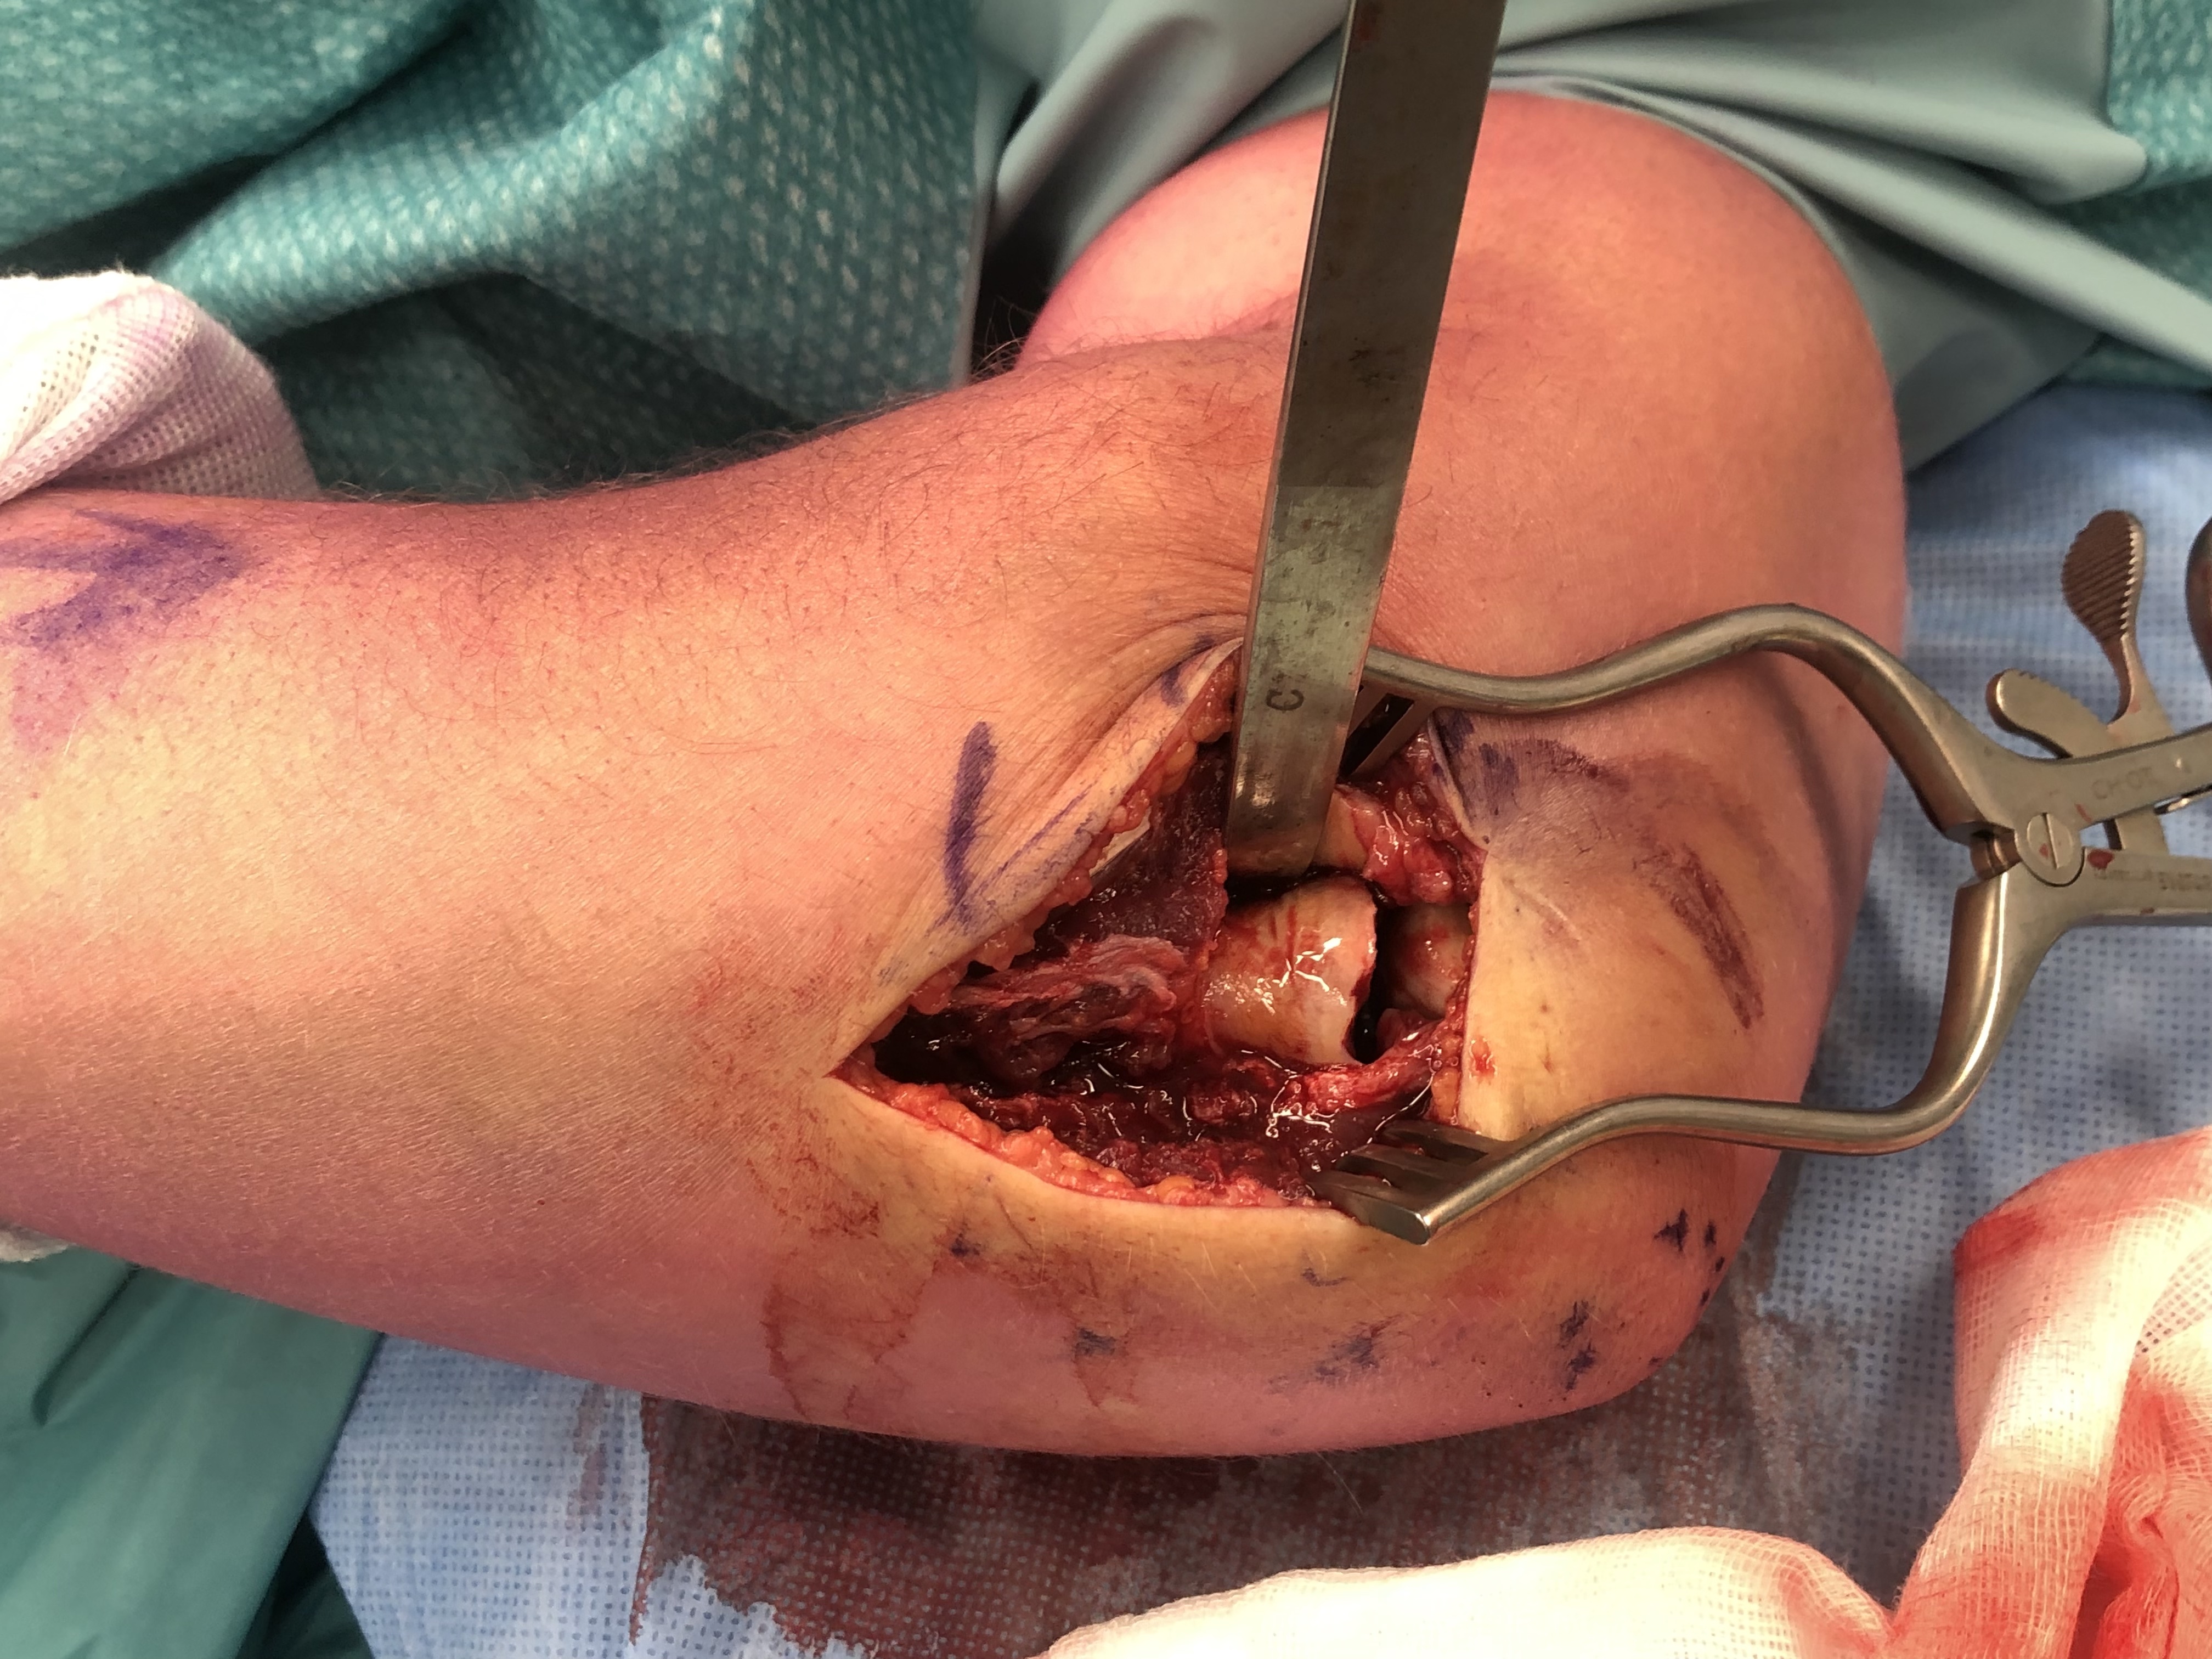

Technique

Vumedi radial head ORIF video 2

Kocher / Kaplan approach

- dissect muscles off capsule

- divide capsule in line with incision / create anterior and posterior flaps

- pronate forearm to protect PIN

- no Hohmann retractors anteriorly and limit distal dissection

- reduce fracture

Technique Modular Titanium Radial Head Arthroplasty

Lateral approach to elbow / Kaplans or Kocher

- open capsule

- divide annular ligaments

- excise radial head fragments

- use fragments to estimate diameter and thickness of radial head

- if in doubt, downsize

- deliver radial neck

- do not place Hohman retractor anteriorly to protect PIN

- ensure neck cut flat to avoid maltracking

- want 60% contact of radial neck with prosthesis

- insert trial broaches into neck

- insert trial head diameter and neck length

- check no overstuffing on xray

- insert prosthesis

- repair annular ligament

- inspect +/- repair LCL